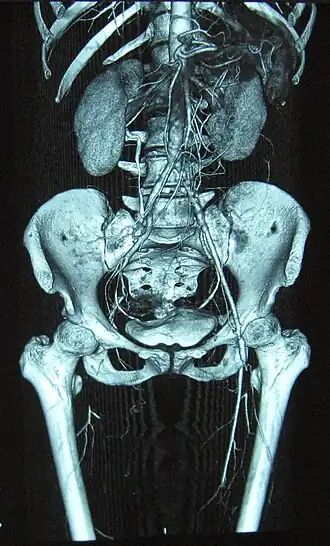

Volledige occlusie van de rechter- en stenose van de linkerdijbeenslagader bij thrombangiitis obliterans | ||||

De ziekte van Buerger[1][2] of thrombangiitis obliterans[5][3] is een chronische ontsteking van de bloedvaten. Deze leidt uiteindelijk tot vaatschade en het ontstaan van trombose.